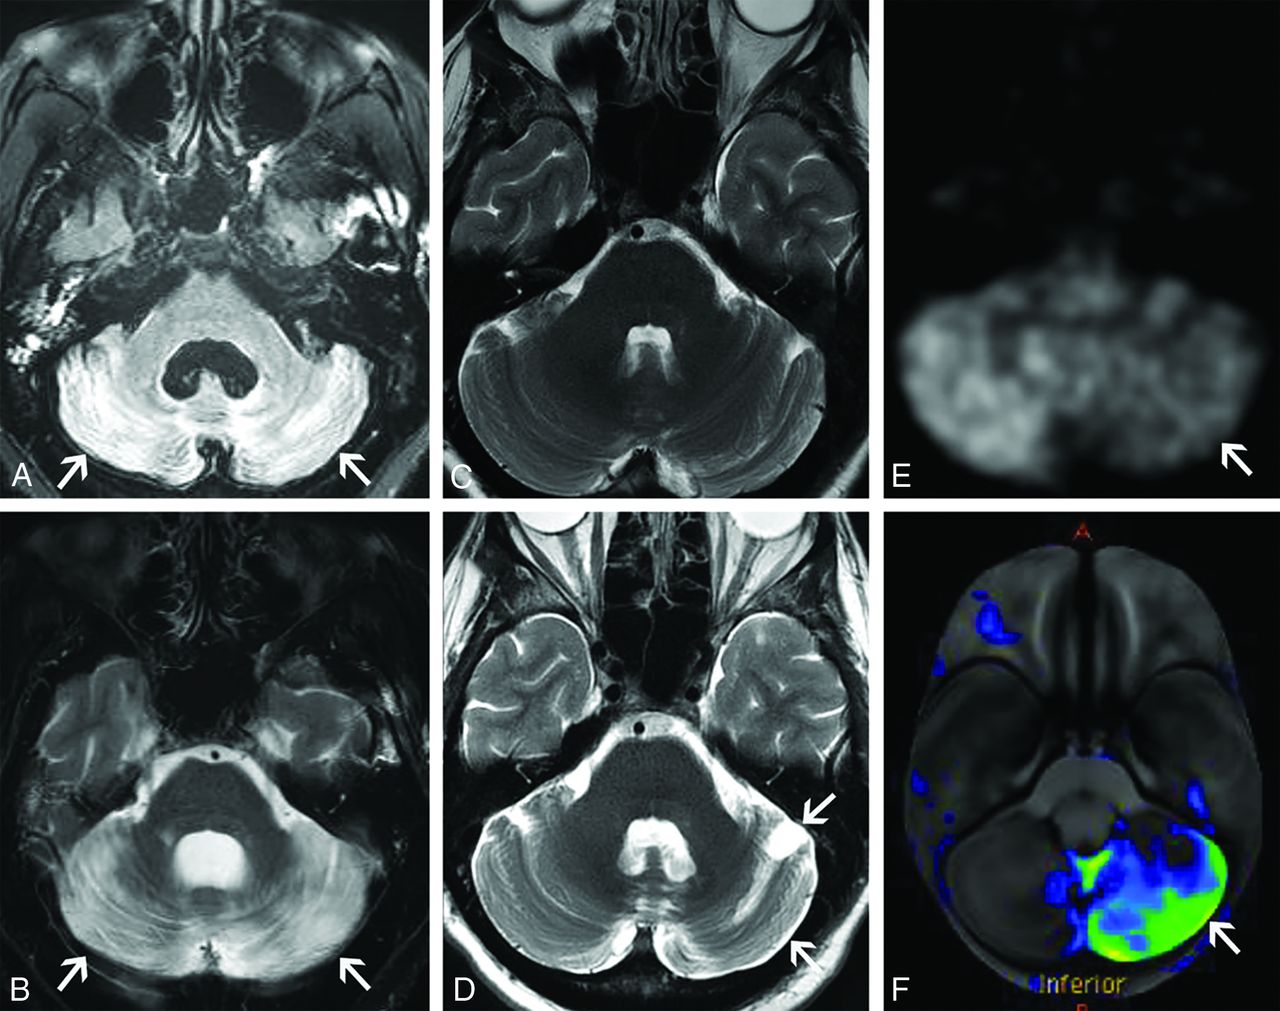

Subacute paraneoplastic cerebellar ataxia (A and B). A 58-year-old woman presented with headaches, vertigo, and ataxia that had progressed over a period of weeks. CSF analysis showed a high titer of PCA-1 autoantibodies. After additional work-up, she was found to have metastatic breast adenocarcinoma. Axial FLAIR (A) and T2-weighted (B) images of the brain show marked T2 hyperintensity diffusely involving both cerebellar hemispheres (A and B, arrows). No enhancement was seen on postgadolinium images (not shown). The patient was diagnosed with paraneoplastic cerebellar degeneration. She had mild improvement in her neurologic symptoms with high-dose corticosteroids but remained wheelchair dependent. Chronic paraneoplastic cerebellar ataxia (C–F). A 56-year-old woman presented with progressive ataxia over a period of several months. Paraneoplastic serum antibody panel revealed anti-G-AchR (ganglionic acetylcholine receptor) antibodies, and CSF analysis revealed increased protein concentration and high IgG levels. Initial axial T2-weighted image of the brain (C) and subsequent axial T2-weighted image from an examination several months later (D) show interval development of mild left cerebellar atrophy (D, arrows). FDG-PET axial source image of the brain (E) and processed surface rendering of the brain compared with age-matched control participants (F) show marked hypometabolism within the left cerebellar hemisphere (E and F, arrows). No cerebral lesion was present to suggest crossed cerebellar diaschisis. Review of prior records noted an FDG-avid thyroid lesion found to be a follicular neoplasm on resection. She was diagnosed with paraneoplastic cerebellar degeneration with chronic atrophic features. Her symptoms have been stable on cyclophosphamide with pulsed corticosteroids.